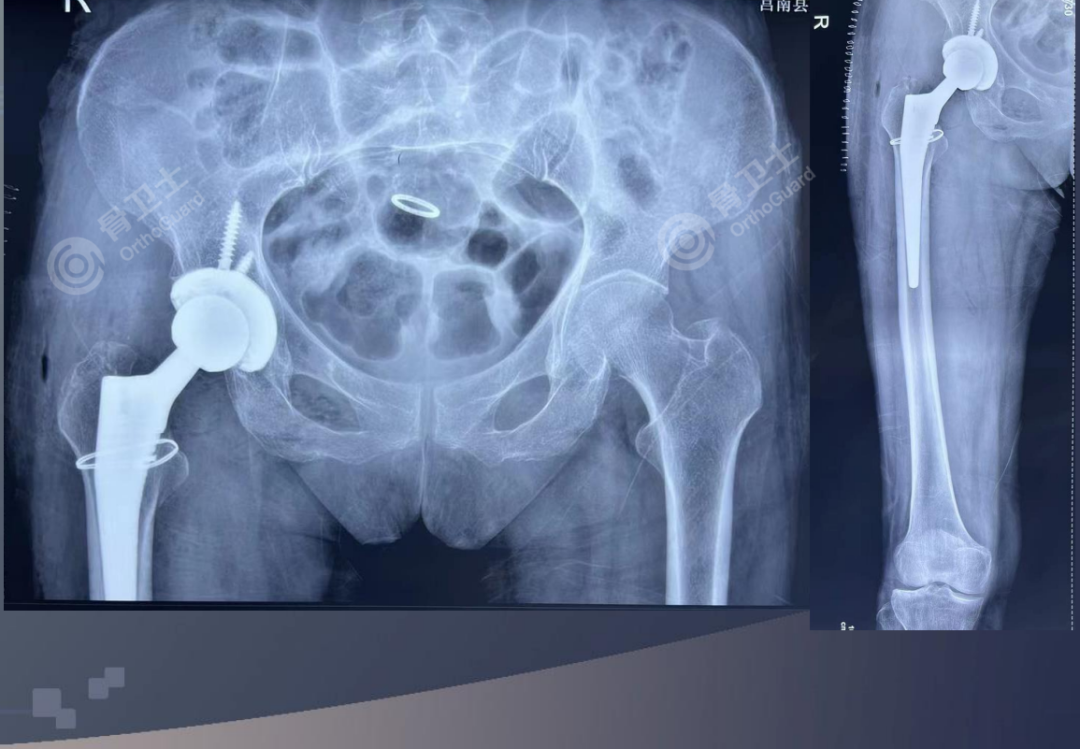

▲患者术前影像

治疗方案:右人工全髋关节置换术。

周乙雄教授表示,该患者的主要问题在心内科方面,有过脑梗,换过心脏瓣膜,在内科保驾护航的情况下,患者骨头质量不错,做全髋关节置换可以。在手术过程中,要注意手术的速度,全髋关节置换的出血量比半髋关节置换出血量多,需要提前备好血。对于是否使用氨甲环酸,要根据患者的情况,征求心内科医生的意见。关于抗凝药物问题,周乙雄教授建议,在征得心内科医生意见后,要在术后12小时开始使用抗凝药物,直至出院,出院后也需要使用一段时间的抗凝药物,嘱患者定期复查。